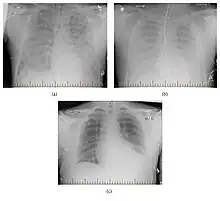

| Hantavirus pulmonary syndrome on chest X-ray | |